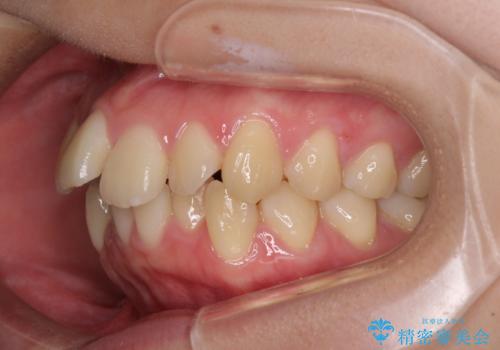

- 前歯のデコボコと突出感を気にして来院された患者様です。

上下左右第一小臼歯4本を抜歯して、積極的に口元を引っ込めるよう、ワイヤー装置にて矯正治療を行うこととしました。